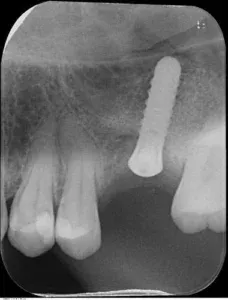

La perdita dei molari superiori lascia in nella maggior parte dei casi una quantità ossea molto ridotta per l’estensione dei seni paranasali (cavità appartenenti al sistema aereo nasale, atte al riscaldamento dell’aria inalata), tale da non permettere l’inserimento impiantare nel modo classico.

Al fine di riabilitare l’elemento dentale perso evitando soluzioni più invasive come protesi mobili o ponti che vanno ad intaccare gli elementi attigui alla perdita dentale è possibile effettuare il posizionamento di un impianto mediante una tecnica di rigenerazione ossea chiamata rialzo di seno mascellare.

–l’approccio crestale che permette l’inserimento immediato dell’impianto con contestuale inserimento di osso sintetico. Questi sono i casi di presenza ossea residua di almeno 4 mm. (tempi di guarigione e di carico variano dai 4 ai 6 mesi)